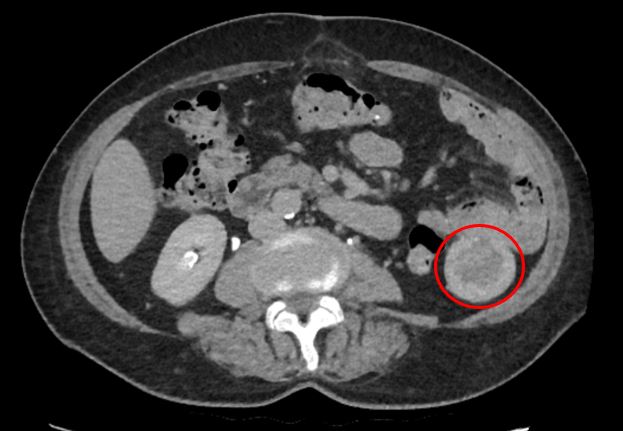

По результатам КТ живота с контрастированием выявлены неорганные образования в брюшной полости, расположенные между петлями кишечника с выраженной фиброзной капсулой, а также состояние после спленэктомии и консолидированные переломы ребер слева. Учитывая анамнез, одним из самых вероятных подозрений стало возможное наличие «инкапсулированных инородных тел».

1. Под брыжейкой тонкой кишки крупное образование размерами около 7-8 см, оно имело плотный неразделимый контакт с петлей тощей кишки на расстоянии 40 см от связки Трейца, выполнено вскрытие его капсулы, при котором опорожнилось около 30 мл гноя.